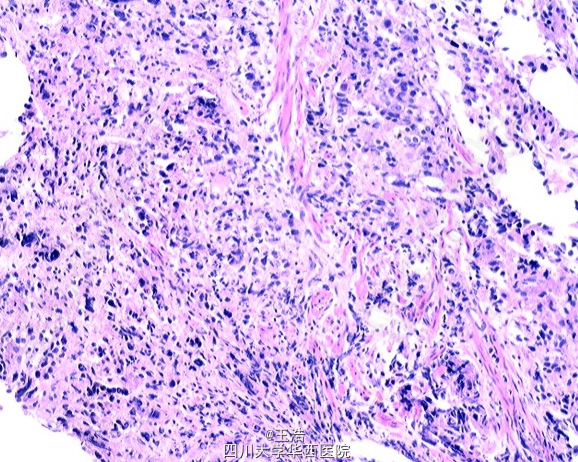

遂行直肠镜活检,提示低分化腺癌。免疫组化提示PSA(+), CK20(-), CDX2(-), Villin(+) ,P504S(+)。通过既往史以及目前的资料分析,患者直肠腺癌可能与前列腺癌有关。遂建议患者行新辅助化疗,以便进一步手术治疗。

前列腺最常见转移至骨,肺和肝脏。此病例为前列腺癌转移至直肠,非常少见,且目前其转移途径尚不完全清楚,主要包括直接侵犯和远处转移。前列腺癌转移至邻近器官非常罕见。Oncol Lett. 2015 Jun; doi: 10.3892/ol.2015.3100